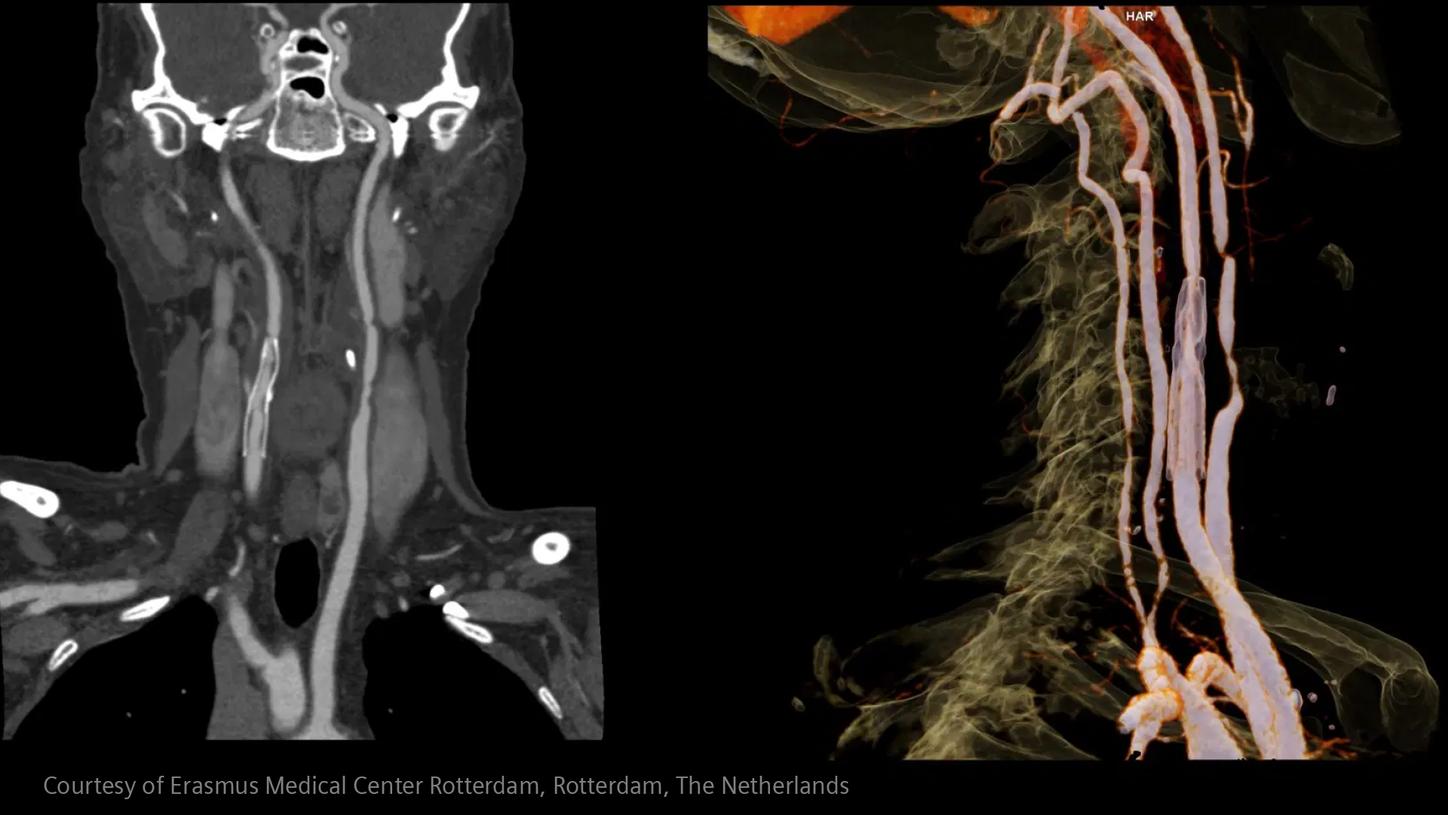

Im Bereich der Schlaganfallversorgung zählt jede Sekunde . Schnelle und präzise Bildgebung ist entscheidend, um das Ausmaß der Hirnschädigung zu beurteilen und die sofortige Behandlung einzusteuern. Angiographie, MRT, CT, Labordiagnostik und Ultraschall sind unverzichtbare Werkzeuge, um Schlaganfalltyp, -bereich und -schwere zu bestimmen. Durch technologische Fortschritte in der Bildgebung sind heute noch schnellere Aufnahmen, eine bessere Auflösung und eine optimierte Darstellung von Gehirnstrukturen und Blutgefäßen möglich. Innovationen wie Perfusionsbildgebung, Echtzeit-Gefäßkartierung und KI-gestützte Diagnostik revolutionieren die Abläufe bei Schlaganfällen und ermöglichen präzise zeitnahe Interventionen.